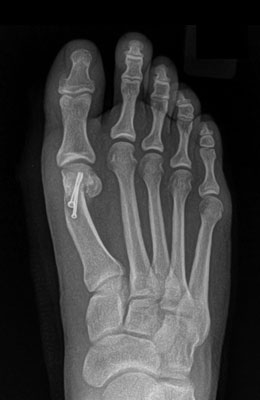

Before

After

Osteotomy Bunionectomy after

Osteotomy Bunionectomy

In this procedure (also known as an “Austin Bunionectomy), a cut in the bone was made, and the bone was shifted to realign the joint. A screw was placed to hold this new alignment in place. Notice the improved alignment of the great toe joint.